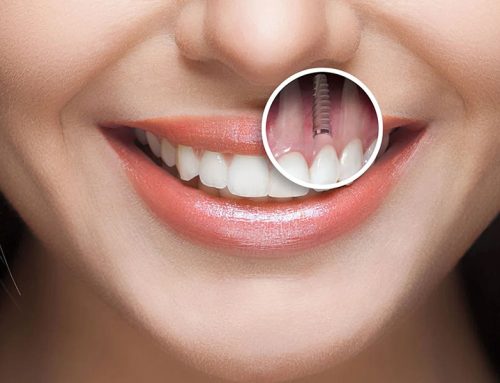

دندانها، این اجزای کوچک اما حیاتی، نقشی اساسی در زیبایی، تکلم و از همه مهمتر تغذیه ما ایفا میکنند. از دست دادن دندان، خواه بر اثر حادثه، بیماری یا کهولت سن میتواند تأثیری عمیق بر کیفیت زندگی داشته باشد. خوشبختانه، علم دندانپزشکی مدرن راه حلی کارآمد و دائمی برای این مشکل ارائه کرده است: ایمپلنت دندان. اما سوالی که مطرح میشود این است که بهترین سن انجام ایمپلنت دندان چه زمانی است؟ در این مقاله به بررسی دقیق سن مناسب ایمپلنت دندان میپردازیم و تلاش میکنیم تا با ارائه اطلاعاتی جامع و کاربردی، شما را در این مسیر همراهی کنیم.

به طور کلی، بهترین سن انجام ایمپلنت دندان زمانی است که رشد فک به طور کامل متوقف شده باشد. این بدان معنا است که استخوان فک به حداکثر رشد خود رسیده و ثبات کافی برای پشتیبانی از ایمپلنت را دارد. معمولاً، حداقل سن ایمپلنت دندان از حدود سن ۱۸ سالگی به بعد است؛ زمانی که فرم و رشد فک به حد کافی رسیده است و احتمال بروز مشکلات ناشی از تغییرات رشد فک به حداقل میرسد.

همانطور که اشاره شد، حداقل سن ایمپلنت دندان زمانی است که رشد فک به پایان رسیده و استخوان فک به ثبات رسیده باشد. متخصصان دندانپزشکی توصیه میکنند که ایمپلنت دندان تا زمان تکمیل رشد استخوان فک انجام نشود. به طور معمول، رشد استخوان فک در دختران تا سنین ۱۶ تا ۱۸ سالگی و در پسران تا سنین ۱۸ تا ۲۱ سالگی ادامه دارد.

اگر ایمپلنت قبل از پایان رشد فک انجام شود، ممکن است موقعیت ایمپلنت با رشد استخوان فک تغییر کند. این تغییر موقعیت میتواند منجر به مشکلات زیبایی و عملکردی شود. به عنوان مثال، ممکن است دندان ایمپلنت شده به درستی با سایر دندانها همتراز نباشد یا باعث بروز مشکلات در جویدن و صحبت کردن شود. همچنین، قرار دادن ایمپلنت قبل از پایان رشد فک میتواند به استخوان فک آسیب برساند و روند رشد طبیعی آن را مختل کند.